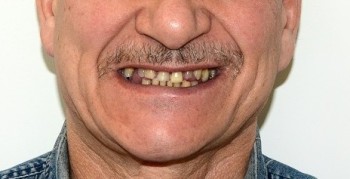

21 работа в портфолио